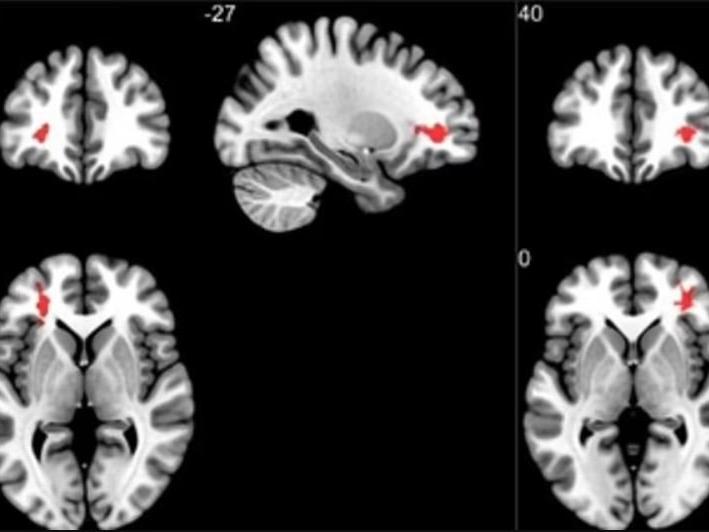

Bilim insanları kırmızıyla işaretlenen bölgelerde değişim meydana geldiğini açıkladı.

Beynin kendini ifade etme ve bedensel hareketlerle ilgili noktalarında bu değişikliğin meydana geldiği belirtilirken beyinde yorgunluk, baş ağrısı ve kavrama yeteneğini yöneten bölgelerde plaklar oluştuğu da ortaya çıktı.